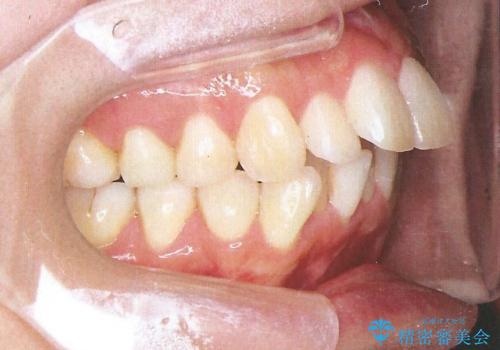

裏側装置で出っ歯の矯正治療

- 出っ歯を目立たない器具で治療したいとのことで来院されました。

上顎の前から4番目の歯を両側抜歯して、上下裏側の装置で前歯を引っ込める計画としました。